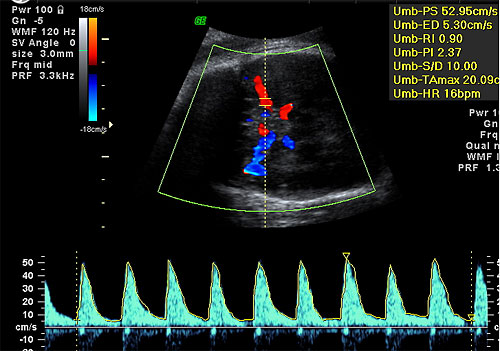

Normal MCA of 52.9 cm seconds

at 32 weeks in a Duffy

sensitized patient

2. Umbilical Arteries — contains 40% of fetal ventricular output in both arteries. Traditionally the systolic flow to diastolic flow or S/D ratio has been used to monitor fetuses at risk. The umbilical Doppler has been particularly useful in managing patients with IUGR, preeclampsia, complicated medical illnesses (diabetes, lupus, etc). (Harrington K, Carpenter RG, Nguyen M, Campbell S. Changes observed in Doppler studies of the fetal circulation in pregnancies complicated by pre-eclampsia or the delivery of a small-for-gestational baby. I. Cross-sectional analysis. Ultrasound Obstet Gynecol 1995;6:19-28. & Pattinson RC, Norman K, Odendaal HJ. The role of Doppler velocimetry in the management of high risk pregnancies. Br J Obstet Gynaecol 1994;101:114-120. & Trudinger BJ, Cook CM, Giles WB, Ng S, Fong E, Connelly A, Wilcox W. Fetal umbilical artery velocity waveforms and subsequent neonatal outcome. Br J Obstet Gynaecol 1991;98:378-84) The ranges are gestationally determined with slightly higher S/D ratios (> 2.5-4.0) in early gestations prior to 24 weeks and the lower S/D ratios ( < 3.0) greater 24 weeks. The absence of end diastolic or reversed end diastolic flow is particularly worrisome. Most believe that the absence or reversed flow in the umbilical artery S/D ratio means a very high risk of stillbirth within 48-72 hours. (Karsdorp VH, Van Vugt JM, van Geijn HP, Kostense PJ, Arduini D, Montenegro N, Todros T. Clinical significance of absent or reversed end diastolic velocity waveforms in umbilical artery. Lancet 1994;344:1664-8 & Kurkinen-Raty M, Kivela A, Jouppila P. The clinical significance of an absent end-diastolic velocity in the umbilical artery detected before the 34th week of pregnancy. Acta Obstet Gynecol Scand 1997;76:398-404)

More recently, the pulsatility index (PI) has been used since it is not affected by the reverse or absence of end-diastolic flow. Reference ranges are used for the 5th and 95th percentiles. (Harrington K, Carpenter RG, Nguyen M, Campbell S. Changes observed in Doppler studies of the fetal circulation in pregnancies complicated by pre-eclampsia or the delivery of a small-for-gestational baby. I. Cross-sectional analysis. Ultrasound Obstet Gynecol 1995;6:19-28.)

3. Middle Cerebral Artery (MCA) — This vessel has been used to detect fetal cerebral blood flow for evaluation of IUGR, medical complications (diabetes, lupus), and fetal isoimmunization. It is the easiest of cerebral vessels to identify by color flow with high sensitivity. (Kirkinen P, Muller R, Huch R, Huch A. Blood flow velocity waveforms in human fetal intracranial arteries. Obstet Gynecol 1987;70:617-21 & Woo JS, Liang ST, Lo RL, Chan FY. Middle cerebral artery Doppler flow velocity waveforms. Obstet Gynecol 1987;70:613-16.) The PI of the MCA decreases during the third trimester. Generally the PI ranges from 1.5-2.5 at 22 weeks to approximately 0.8-1.7 at 40 weeks. (Harrington K, Carpenter RG, Nguyen M, Campbell S. Changes observed in Doppler studies of the fetal circulation in pregnancies complicated by pre-eclampsia or the delivery of a small-for-gestational baby. I. Cross-sectional analysis. Ultrasound Obstet Gynecol 1995;6:19-28.) In the IUGR fetus, the mean MCA PI is lower and the mean systolic velocity higher representing a shunting of blood to the head of the fetus to spare the brain.